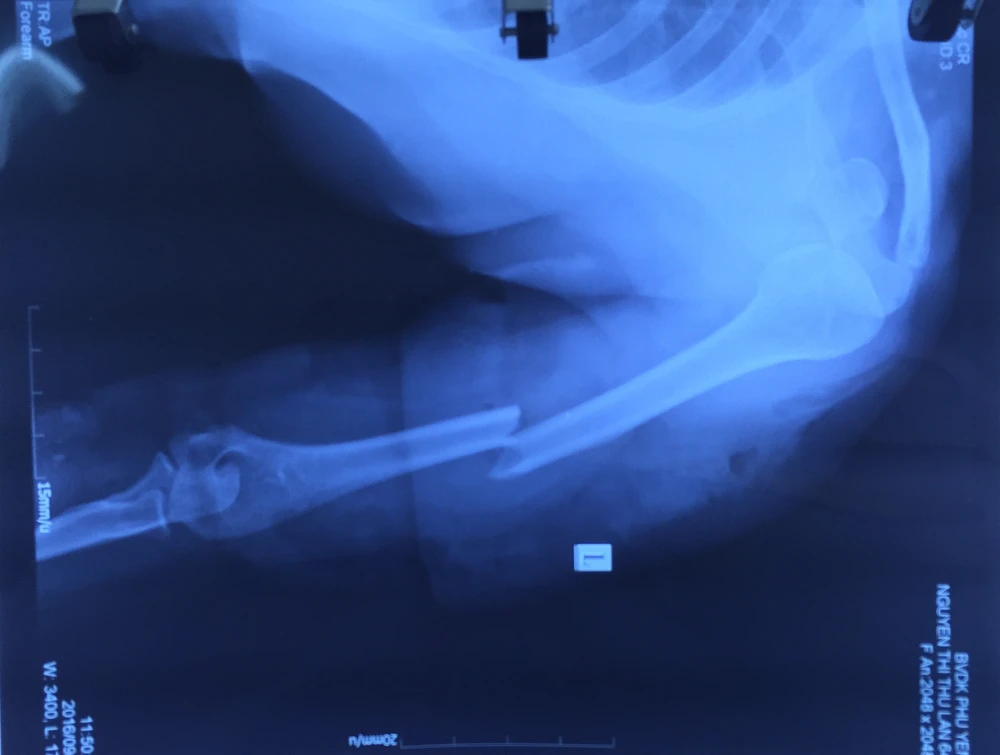

Kết quả chụp X quang cho thấy cánh tay trái bà L. bị gãy. Ảnh: MINH ĐỨC

Trước đó, ngày 9-9, bà L. nhập viện trong tình trạng huyết áp tụt, sốc do chấn thương, xương cánh tay trái bị gãy, dập nát cơ cẳng tay, lột toàn bộ da, bàn tay tím lạnh do tắc động mạch. Người nhà cho biết bà L. bị xe tải nhỏ cán nát cánh tay nên được đưa vô bệnh viện địa phương. Sau khi sơ cứu, bệnh viện này cho biết phải cắt bỏ cánh tay nên gia đình đưa bà L. lên BV Nhân dân 115.